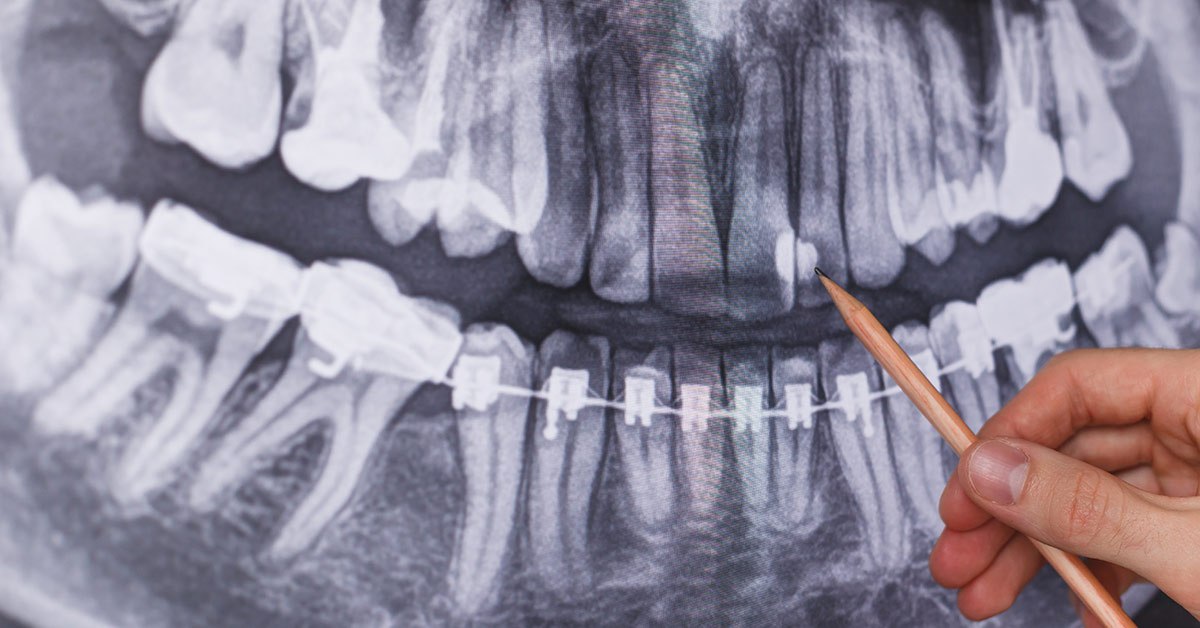

O radiografie dentara este un instrument valoros in stomatologie, reprezentand o imagine a dintilor pacientului, pe baza careia medicul stomatolog evalueaza sanatatea orala. Radiografia dentara este o componenta esentiala in evaluarea starii de sanatate orala a unui pacient.

Prin radiografie dentara, medicul stomatolog poate sa examineze zonele dintilor care nu sunt accesibile cu ochiul liber. Aceasta metoda permite unui stomatolog sa investigheze, cu precizie, problema dentara a pacientului, astfel incat sa poata furniza cele mai bune optiuni de tratament.

Printr-o radiografie dentara, stomatologul capata abilitatea sa vada intre dintii si in interiorul dintilor pacientilor. Totodata, acesta are acces sa vada radacina dintilor, oasele aflate sub gingie.

O radiografie dentara poate sa dezvaluie probleme complicate, abcese, boli parodontale, pierdere osoasa, precum si starea canalelor radiculare, a plombelor si a puntilor dentare.

Radiografie dentara panoramica (numita si ortopantomograma sau OPG): se recomanda la consultul stomatologic initial. Ofera o imagine de ansamblu a tuturor dintilor si a raportului acestora cu formatiunile anatomice vecine. Măreste cu 25-35%.